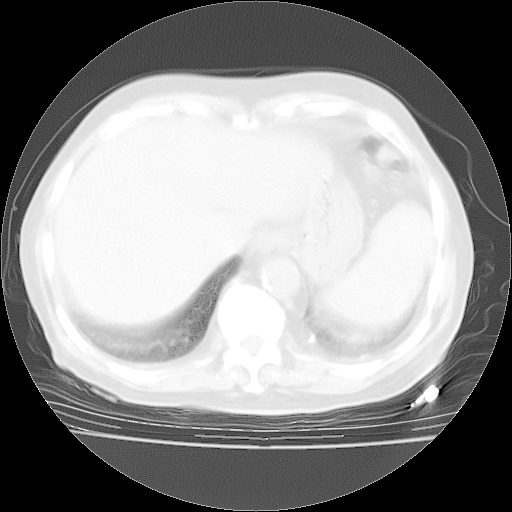

4月28日肺部CT——再次出现类似去年5月9日——透光度降低,“间质性”改变。

4月28日肺部CT——再次出现类似去年5月9日——磨玻璃样、间有“粟粒样”改变。